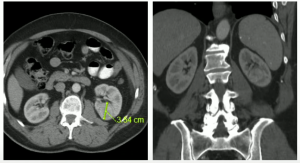

A 70-year-old man with well controlled hypertension, hyperlipidemia, normal renal function, discovered a 3.5mm endophytic left renal mass.

In July 2012, we performed an uneventful partial nephrectomy with robotic assistance.

Patient ended up pT1a staging. With post-operative serum creatinine of 0.9. Which was a good response to treatment.